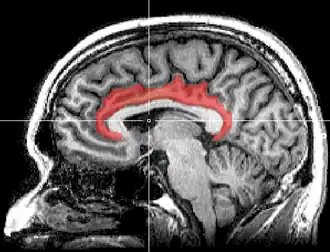

Le gyrus cingulaire est un gyrus du lobe limbique du cortex cérébral. Il est situé sur la face médiale des hémisphères, au-dessus du corps calleux. Au-dessus, il est séparé du gyrus frontal supérieur par le sillon cingulaire et du précuneus par le sillon sous-pariétal. En dessous, sa limite est le sillon du corps calleux. Au niveau du splénium du corps calleux, le gyrus cingulaire se rétrécit dans l'isthme qui se poursuit par le gyrus parahippocampique[1].